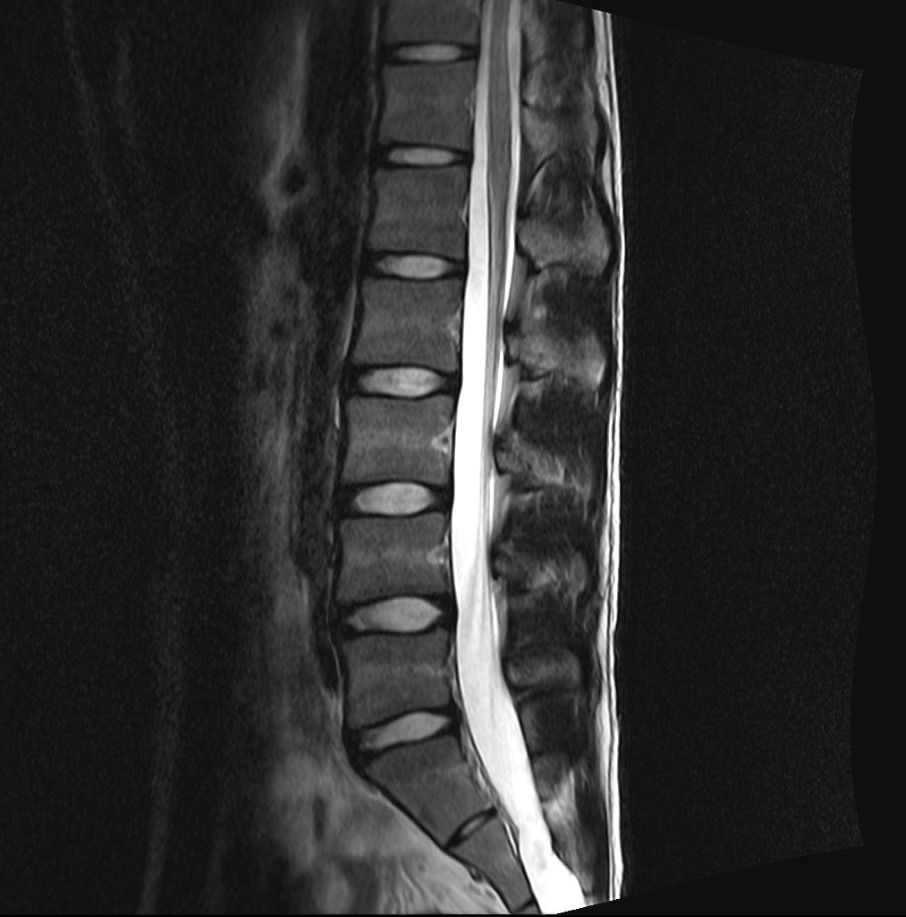

Mrl 보시고 확인좀 부탁드리겠습니다 교통사고가 나서 허리가 안좋아서 Mrl 촬영했습니다 근데 디스크가 있다고 합니다 한방병원에서는 있다고 하고

허리전문병원에서는 없다고 합니다

누구 말을 믿어야할지 모르겠어요 바쁘시겠지만 부탁드리겠습니다

mri상으로볼때에는 디스크가 약간 나와있는걸로보이지만 신경을 자극한다거나 다른문제는없어보이는데요 일단 불편감이지속되고있다면 근육의긴장이나 염증으로인해서 그러는증상일수도있습니다

병원마다 MRI 결과를 다르게 보는 이유로는 디스크가 살짝 튀어나와 있지만 신경을 누르지는 않거나 그 경계에 있다면 그럴 수 있으며 올려주신 MRI사진 같은 경우 단면 사진으로 단면사진만으로는 평가하기 힘들 것으로 생각되며 일단 올려놓으신 영상만 보았을때는 큰 문제는 없는걸로 보이며 자세한 상태는 영상을 가지고 전문 병원에 방문하시어 제차 검사 받아보시는게 좋을 것으로 생각됩니다.

올려주신 사진상에서 허리 아래부위에 존재하는 디스크가 약간의 돌출이 보이는데요, 신경을 압박하는 것처럼 보이지는 않습니다.

디스크 돌출이나 경미한 추간판 탈출증으로 보이는데요, 각 병원에서 견해에 따라 허리디스크로 진단하거나 하지 않는 것으로 보입니다.